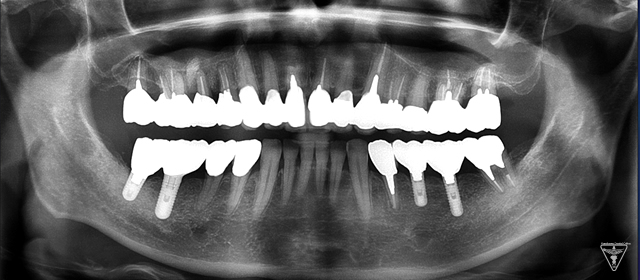

Xrayから向かって左上の部分の歯を支える骨が溶け、歯がぐらぐらになっている状態を示します。(赤丸の部位)

赤丸部位は骨の再生の状態を示す。

垂直的骨欠損に対して再生が確認できる